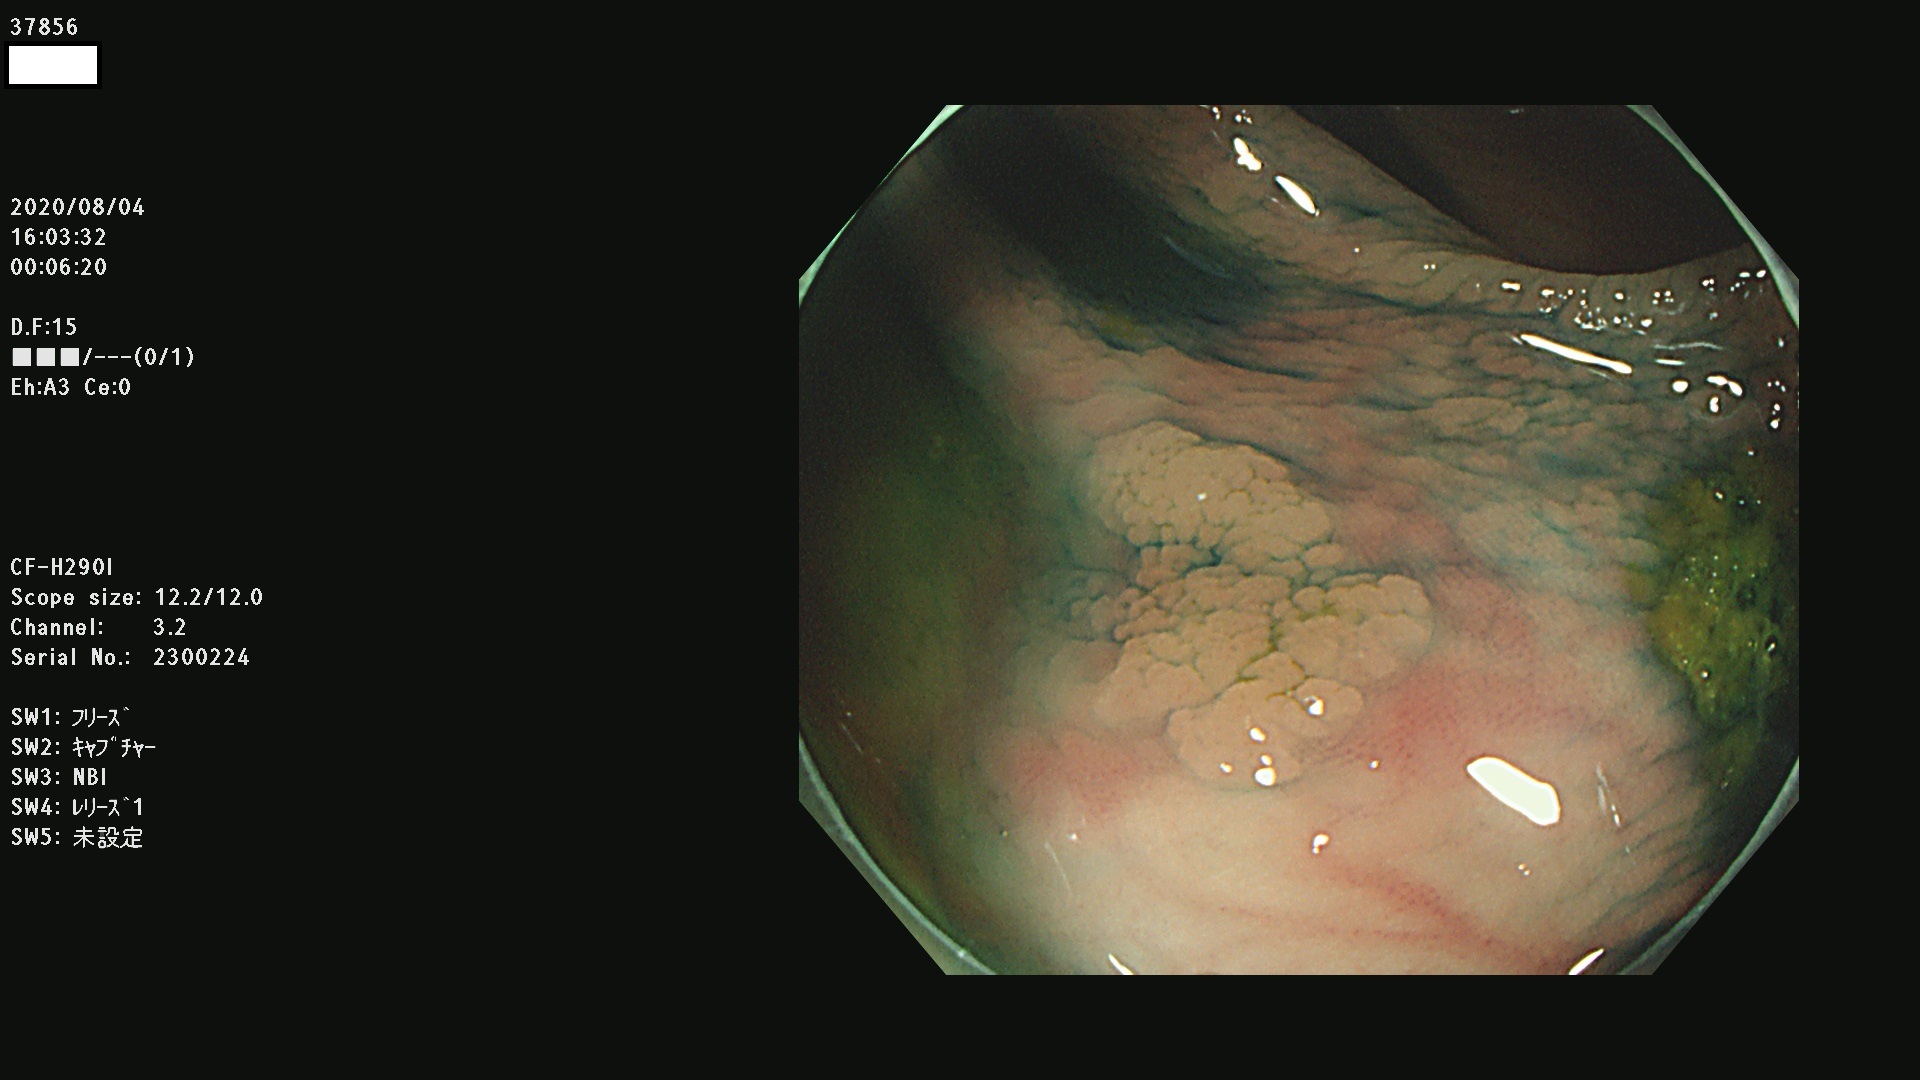

腺腫発見率 75 % (カルテ番号 37800〜37899の100名の方の検査結果で集計)大腸癌検診最新情報

以下のカルテ番号の方に腺腫(Adenoma,Group3〜5)が見つかりました(集計法)

37800(SSAPのみ) 37801 37802 37803 37804 37805 37806 37807 37808 37809(SSAPのみ) 37810 37811 37812 37813 37814 37815 37817 37818 37819 37820 37821 37822 37824 37825 37826 37827 37828 37829 37832 37833 37836 37837(SSAPのみ) 37839 37840 37842 37844 37845(SSAPのみ) 37847 37849 37850 37851 37852 37853(SSAPのみ) 37855 37856 37857 37860 37861 37862 37863 37864 37867 37868 37871 37874 37876 37877 37879 37880 37881 37882 37883 37886 37887 37888 37889 37890 37891 37892 37893 37894 37896 37897 37898 37899

発見困難で危険性の高い平坦型病変(上記100名より抽出) ![]()